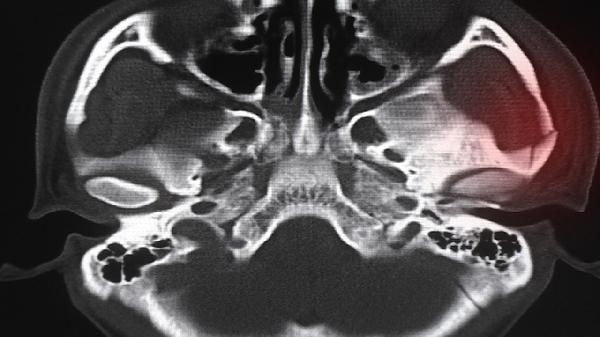

对于类风湿关节炎患者,骨仙片能缓解关节畸形进展。通过抑制破骨细胞过度活化,减少关节骨质侵蚀,配合抗风湿药物使用可改善手指小关节对称性疼痛。需定期监测肝肾功能和影像学变化。